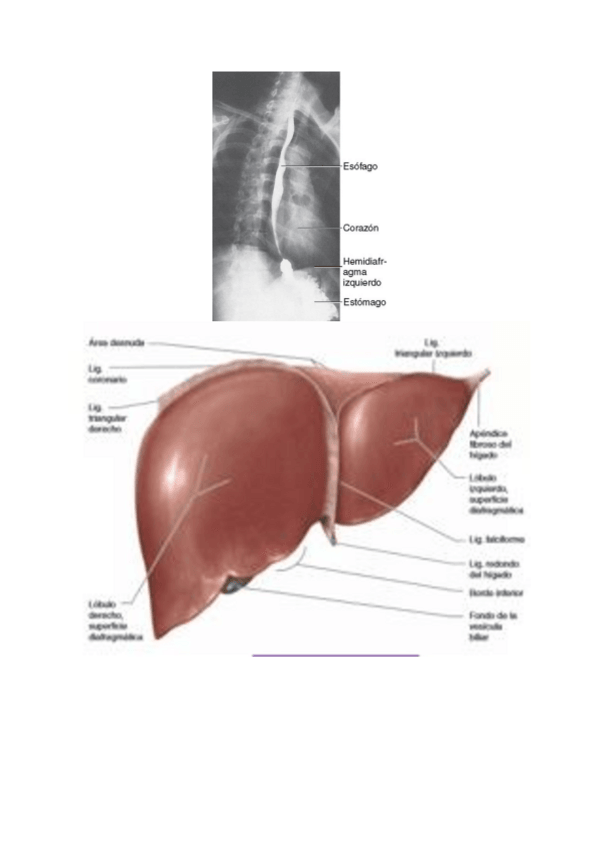

Apuntes - anatomia-imagenes-3-evaluacion.pdf